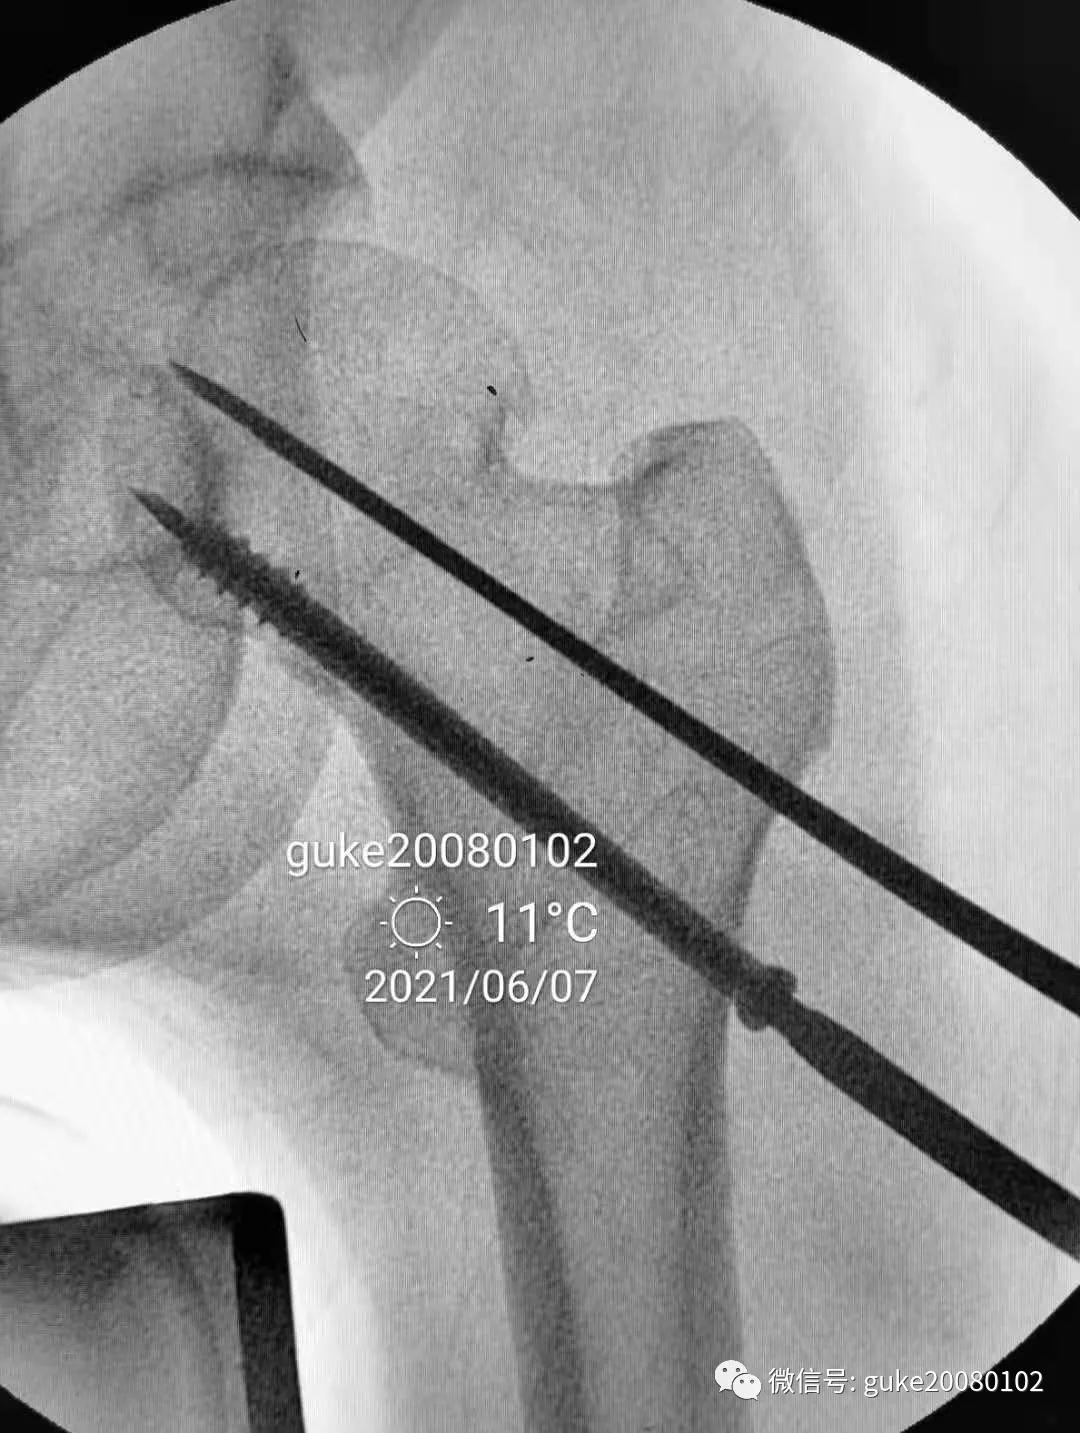

1.正侧位观察骨折复位,骨小梁走形恢复。崁插骨折复位。

2.外侧植入克氏针一枚,临时固定骨折。